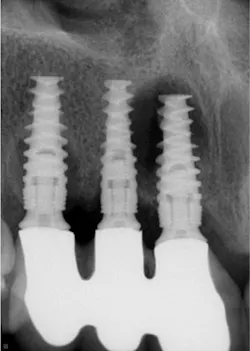

The digital images show only about 50% of the actual depth of small lesions. This often delays tooth restoration, causing unnecessary challenges with greater tooth destruction, more time and material used, wider exposure of restorations to occlusal wear, and potential pulpal damage (figure 2).

Sensors are about 9 mm thick and rigid. They cannot be adapted to the dental arch curvature, and they provide unequal radiation to the teeth and inaccurate identification of caries.

The cost of digital sensors is high and unjustified in the opinions of many dentists. Just like composites mentioned previously, dentists take radiographs many times per day. The manufacturer who overcomes these challenges will rapidly dominate the radiographic market. It is time for manufacturers to improve these inadequate diagnostic issues.